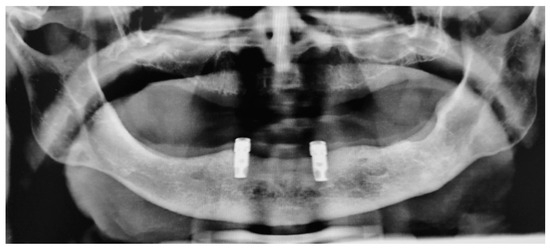

2.1.3. Follow Ups and Implants Insertion

- surgical insertion of two anterior implants in the region of the mandibular canines

- rehabilitation with implant-supported OVD adapting the current complete removable denture, 3 months after implant surgery.

3.1. Case Report